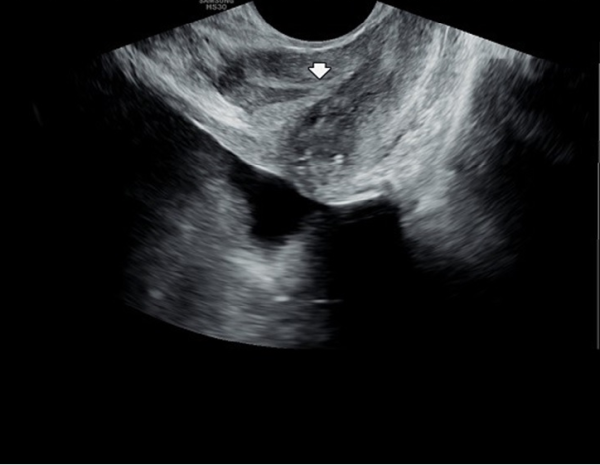

상급 의료 기관에서 회음부 통증과 배뇨장애등의 증상이 치료 되지 않아 내원 당일 경직장 전립선 초음파 검사상 사정관입구의 순환 장애로 사정관 낭종이 관찰되는 경직장 전립선 초음피 사진입니다.

This is a transrectal prostate ultrasound image taken on the day of the patient’s first visit, following persistent perineal pain and urinary symptoms that were not resolved at a tertiary care hospital. The image shows a seminal duct (ejaculatory duct) cyst caused by circulatory obstruction at the duct opening.

주 2~3회 가량 전립선의 표적 치료후 사정관 낭종이 치료 되었으나 사정관 주위에 탈락된 상피 세포의 관리가 필요한 추적 경직장 전립선 초음파 사진입니다.

This is a follow-up transrectal prostate ultrasound image taken after receiving targeted prostate therapy 2 to 3 times per week. The ejaculatory duct cyst has been resolved, but there is a need for continued management of the exfoliated epithelial cells around the ejaculatory ducts.